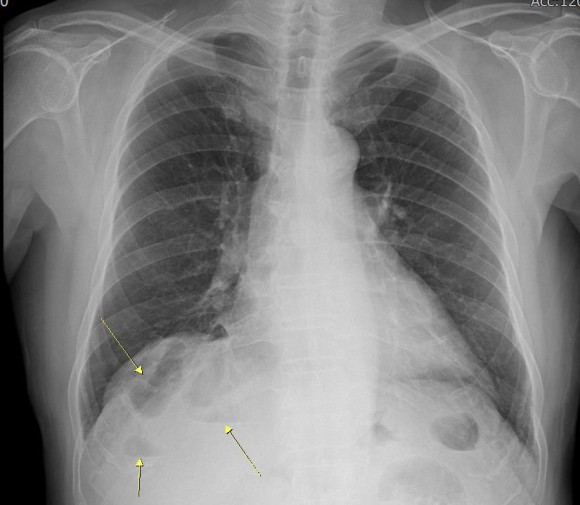

최근 이분의 여러 사진을 검토하는 과정에서 위 사진처럼 횡격막과 간 사이에 대장이 끼어 있는 것이 관찰되었으며, 이 마직막 사진에서는 그 부분의 대장에는 장의 약간의 마비를 시사하는 수면을 볼 수 있다.

이 분의 증상이 이른바 Chilaiditi 증후군이 아닐까 의심된다.이 분처럼 대장이 횡격막과 간 사이에 끼어 있는 현상을 Chilaiditisign이라고 한다. 이것이 확실한 증상을 가져온다는 것이 확인되면 Chilaiditi 증후군으로 진단한다. 그러나 이 병은 진단이 매우 어렵고 증상도 다양하다.

이 병은 19010년 그리스 방사선 의사인 Dimitrios Chilaiditi가 처음 기술했다 뚜렷한 증상은 오른쪽 윗배가 아픈데 다른 병으로는 설명할 수 없으며 이런 현상이 보이자 이 병을 의심한다